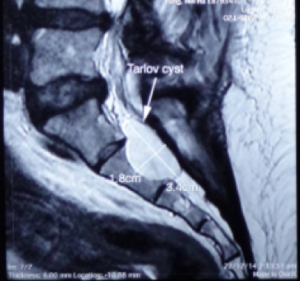

3.4 X 1.8 cm 骶骨第二節骶管襄腫

骶管襄腫一般生長於骶骨的第一節至第三節,內裹充滿了腦脊液, 襄腫可逐漸增大導致馬尾神經線被壓迫, 引起神經根發炎或產生脊髓病變及令骨性結構也被侵入破壞.。磁力共振檢查可清楚分辨骶管襄腫的位置,大小及與硬脊膜和神經根的關係。

一般細小的骶管襄腫多數不會引起任何問題.但如病人的徵狀引起神經缺損而嚴重地影響日常生活, 手術介入可能是最好的選擇。 手術經腦神經外科醫生處理,以微創手術,將襄腫抽吸腦脊液,再封堵阻止脊液進入,然後拿取病人身體的脂肪或肌肉來填塞襄腫空間。( 圖ー , 圖ニ)

3.4 X 1.8 cm 骶骨第二節骶管襄腫

圖二